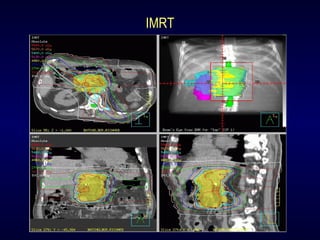

3-D Conformal RT

IMRT

Radiosurgery

Modern SBRT Systems